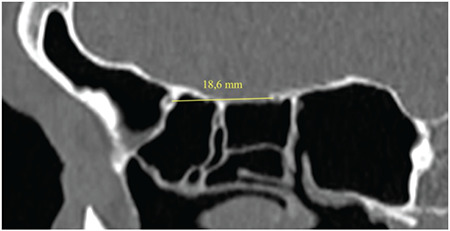

Results: There were 100 patients in this study, of whom 51% (51/100) were female and 49% (49/100) were male. Patient ages ranged from 20 to 84 years. Their average age was 40.92±14.65 years. The distance on CT scan between the posterior and anterior ethmoidal arteries was 13.98±1.95 mm (9.3 to 18.6 mm). This distance in males was significantly higher than female (p=0.001). However, there is no difference in this distance between the left and right side (p=0.67). The distance between the posterior ethmoid artery and skull base ranged from 0 to 5.4 mm. The average distance between the posterior ethmoidal artery and skull base on CT scan was 0.95±0.94 mm. The diameter of the posterior ethmoid artery was 0.57-0.91 mm. The average diameter of the posterior ethmoidal artery on CT scan was 0.76±0.09 mm.